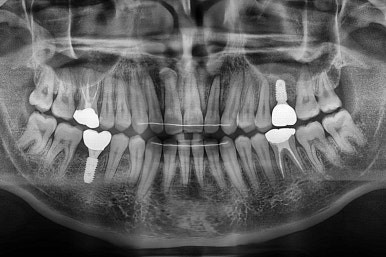

교정치료도 종료 되었고 연산동임플란트 잘 완성이 되었어요.

총 14개월이 걸린 치료였는데 비교적 짧은 기간 내에 틈새도 모으고, 임플란트 및 충치치료도 다 완료를 할 수 있었습니다.

왼쪽이 치료 전, 오른쪽이 연산동임플란트 치료 후 X-ray 사진입니다.

전후 사진을 비교해 볼게요.